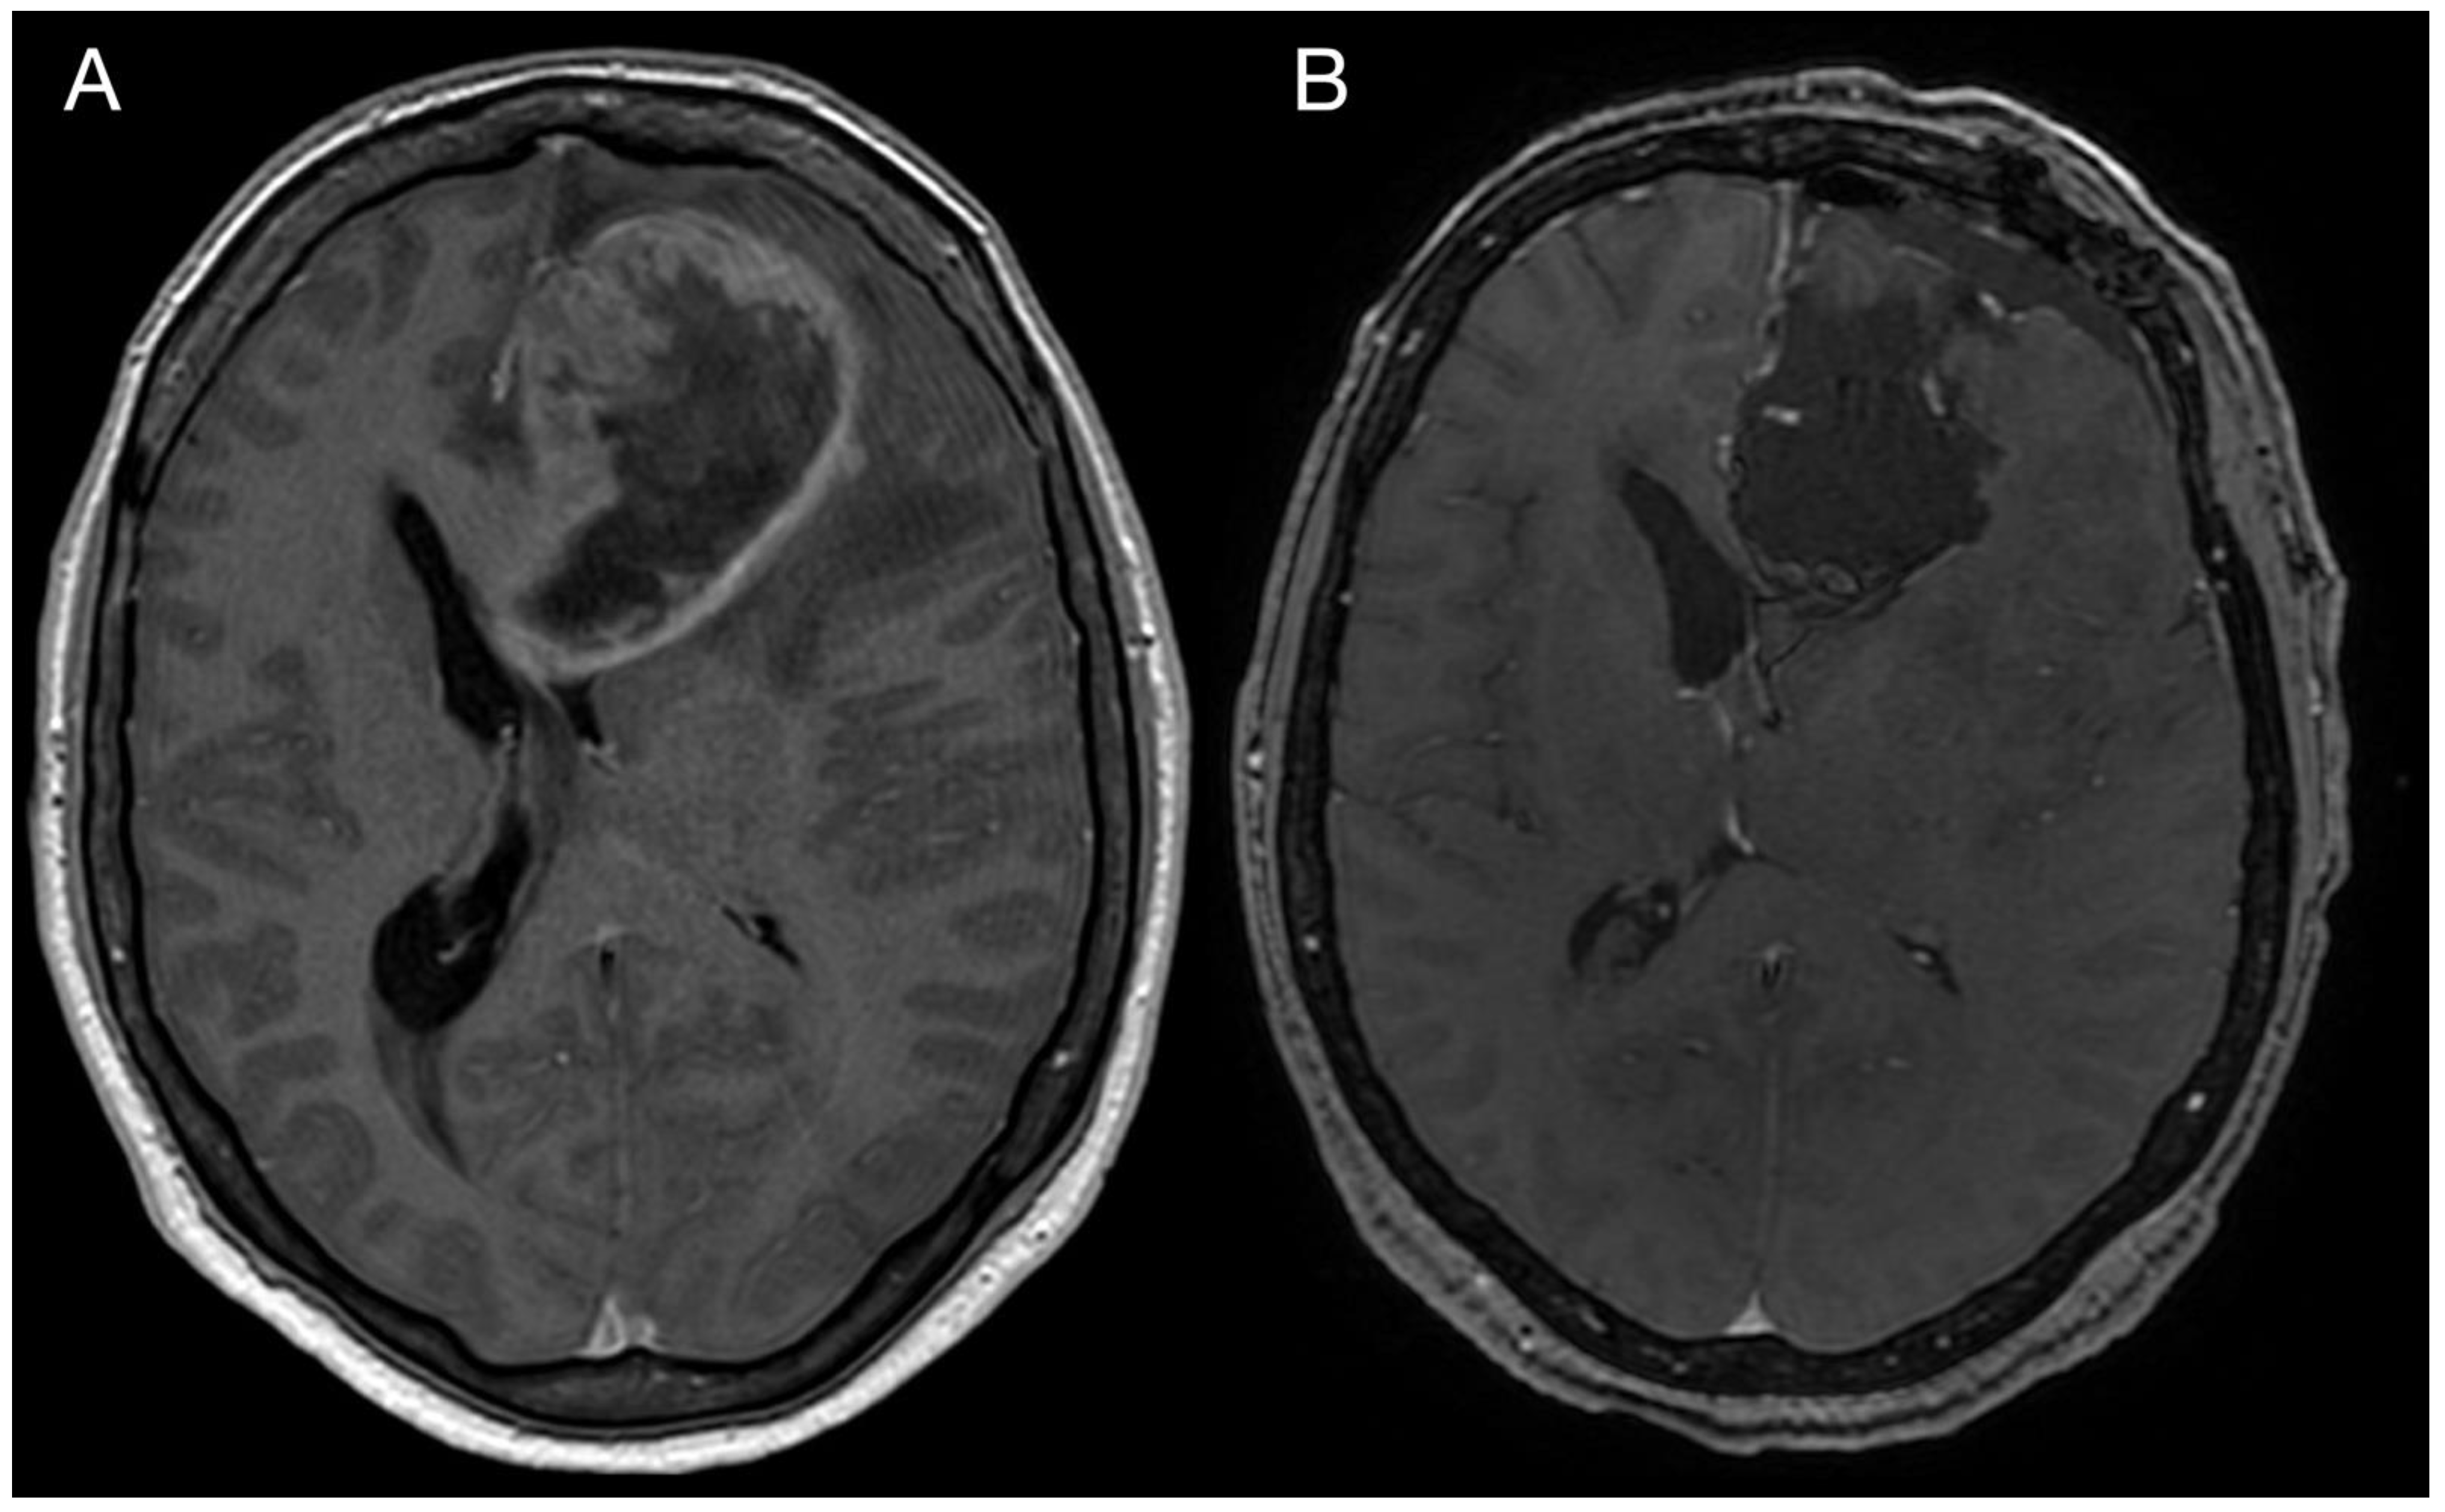

A 43-year-old woman with organic psychosyndrome was examined by a neurologist and subsequently referred to a neurosurgeon with an MRI finding of an intra-axial contrast-enhancing lesion in the left frontal lobe with perilesional edema and midline shift (Figure 1A). The patient underwent MRI-navigated fluorescence-guided surgery using 5-aminolevulinic acid (5-ALA), which led to the opening of the left lateral ventricle due to tumor infiltration of the ventricular wall. Tissue samples from the tumor core and resection margins were collected separately for histological evaluation. Based on an MRI obtained within 48 h after surgery, the extent of resection was marked as a gross total resection (Figure 1B).

Figure 1.

Imaging of the primary brain tumor. Preoperative axial brain MRI (postcontrast T1 weighted images) showing an intra-axial contrast-enhancing lesion in the left frontal lobe with perilesional edema and compression of the adjacent third and lateral cerebral ventricles (A). Postoperative MRI is showing total tumor resection. The resection cavity communicates with the frontal horn of the left lateral ventricle (B).